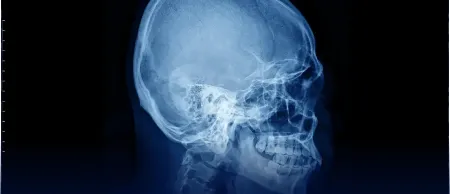

CBCT 3D Imaging at Daghlian Pediatric Dentistry & Sokolowski Orthodontics

CBCT 3D Imaging